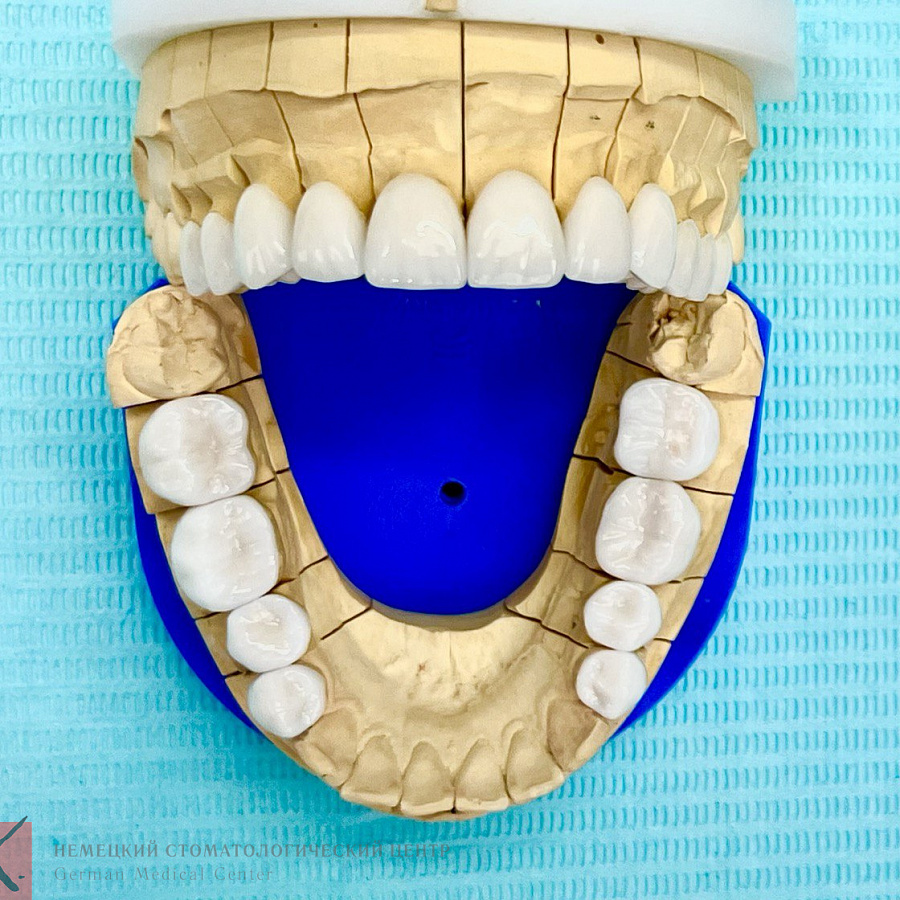

Основная проблема, с которой мы столкнулись - это отсутствие достаточного объема костной ткани для проведения качественной ортодонтии. Поэтому была выполнена частичная ортодонтия - перемещение зубов в имеющейся костной ткани в пределах возможного. Нижняя челюсть зафиксирована в нужном терапевтическом положении, комфортном для сустава. Далее было проведено ортопедическое лечение и реабилитация как боковых, так и передних отделов зубов.